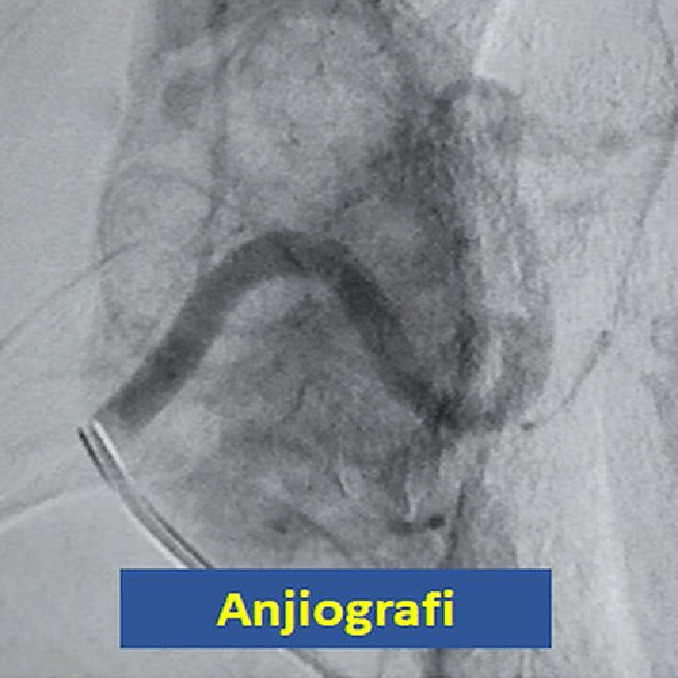

Boynunda dışa doğru büyüyen dev guatr sorunu olan 41 yaşındaki erkek hastamızda, önce anjiografi tekniğiyle embolizasyon yapılarak guatr dokusunu besleyen damarlar tıkanıyor. Daha sonra da 2 kez alkol ablasyonu yapılıyor. Bir yıl sonra boyundaki guatr kitlesinin %90’dan fazla küçüldüğü izleniyor. Bu tür hastalarda, guatrdaki küçülme sonraki yıllarda da devam etmektedir.